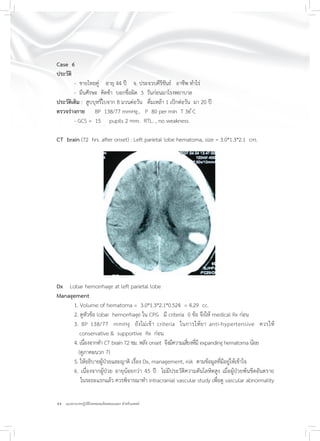

Case 5

ประวัติ

- ชายไทยคู่ อายุ 72 ปี จ. สมุทรปราการ

- ปวดศีรษะ ชอบเดินชนสิ่งของทางด้านซ้าย 2 วัน

ประวัติเดิม : Old CVD, HT , กินยา ASA & other anti-platelet aggregation

ตรวจร่างกาย : BP 140/ 90 mm.Hg, P 98 per min.

- GCS = 15, pupils 3 mm. RTL. BE.

- Left hemianopia

CT brain (48 hrs. after onset) : right occipital lobe hematoma, size = 1.7*2.8*3.0 cm.

Dx Lobar hemorrhage right occipital lobe

Management

1. Volume of hematoma = 1.7*2.8*3.0*0.524 = 7.48 cc.

2. ดูหัวข้อ lobar hemorrhage ใน CPG มี criteria 0 ข้อ จึงให้ medical Rx ก่อน

3. BP 140/90 mmHg ยังไม่เข้า criteria ในการให้ยา anti-hypertensive

ควรให้ยาและสารน้ำเป็น conservative & supportive Rx ก่อน

4. เนื่องจากทำ CT brain 48 ชม. หลัง onset จึงมีความเสี่ยงที่มี expanding hematoma น้อย

(ดูภาคผนวก 7)

5. ให้อธิบายแก่ผู้ป่วยและญาติ เรื่อง Dx, management, risk ตามข้อมูลที่มีอยู่ให้เข้าใจ